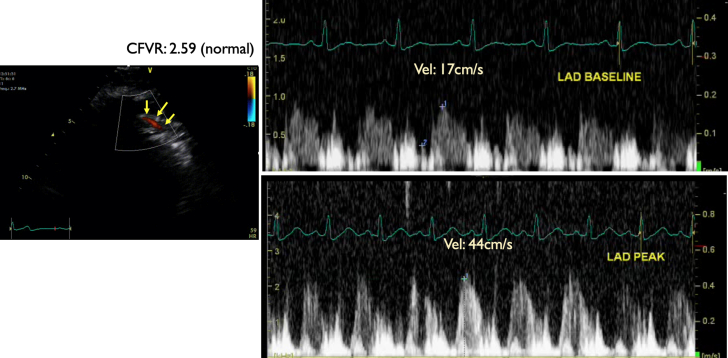

One year after the successful LAD PCI, patient 1 was re-referred for sequential DSE to assess the bystander proximal LCX and right coronary artery disease. DSE was terminated at the end of protocol at 93% of age-predicted maximal heart rate with no symptoms (30 μg/kg/min and 0.10 mg atropine in addition to handgrip exercise; rate–pressure product, 16,159 mm Hg·beats/min). The resting echocardiogram showed no RWMA, and all segments of the left ventricle augmented well during low dose and remained hyperdynamic at peak. The CFV in the distal LAD was 17 cm/s and 44 cm/s at baseline and peak, respectively, in keeping with normal CFVR (2.59) (Figure 4, Figure 5, Figure 6, Video 2). The patient continued with secondary preventive therapy. A low major adverse cardiovascular event risk was concluded.

Figure 5.

Patient 1 Follow-Up: Coronary Flow Velocity by Doppler Echocardiography

One year after percutaneous coronary intervention to proximal left anterior descending coronary artery (LAD) with symptomatic improvement to assess bystander left circumflex coronary artery and right coronary artery stenosis. Coronary flow velocity by Doppler echocardiography in the distal LAD 12 cm/s, indication very low distal flow, consequently severe proximal stenosis. Yellow arrows indicate distal LAD color Doppler flow in diastole. Coronary flow reserve of 44 cm/s/17 cm/s = 2.59 (normal).

As in our patient 1 with typical effort angina, DSE has shown extensive LAD territory ischemia with high-risk features. Interestingly, the reduced resting CFV (10 cm/s) raised the suspicion of severe proximal LAD stenosis already at baseline. Successful PCI to LAD has rendered the patient symptom free. The complimentary power of the RWMA and CFVR assessment was eloquently demonstrated in this same patient (labelled as Patient 1 follow-up), who 1 year after his LAD PCI was re-referred for a sequential DSE and CFVR assessment to address the bystander LCX and right coronary artery lesions. Post-PCI stress echocardiography showed now no inducible ischemia and the CFVR was normal at 2.59.